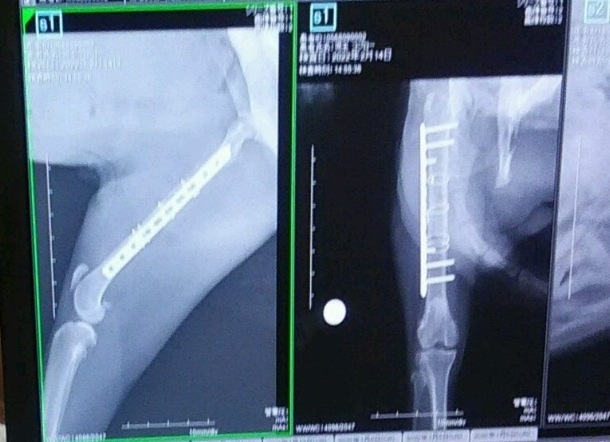

今日は術後のレントゲン撮影に行ってきました。異常もなく順調に回復しているようです。

2/14 レントゲン撮影 6050円